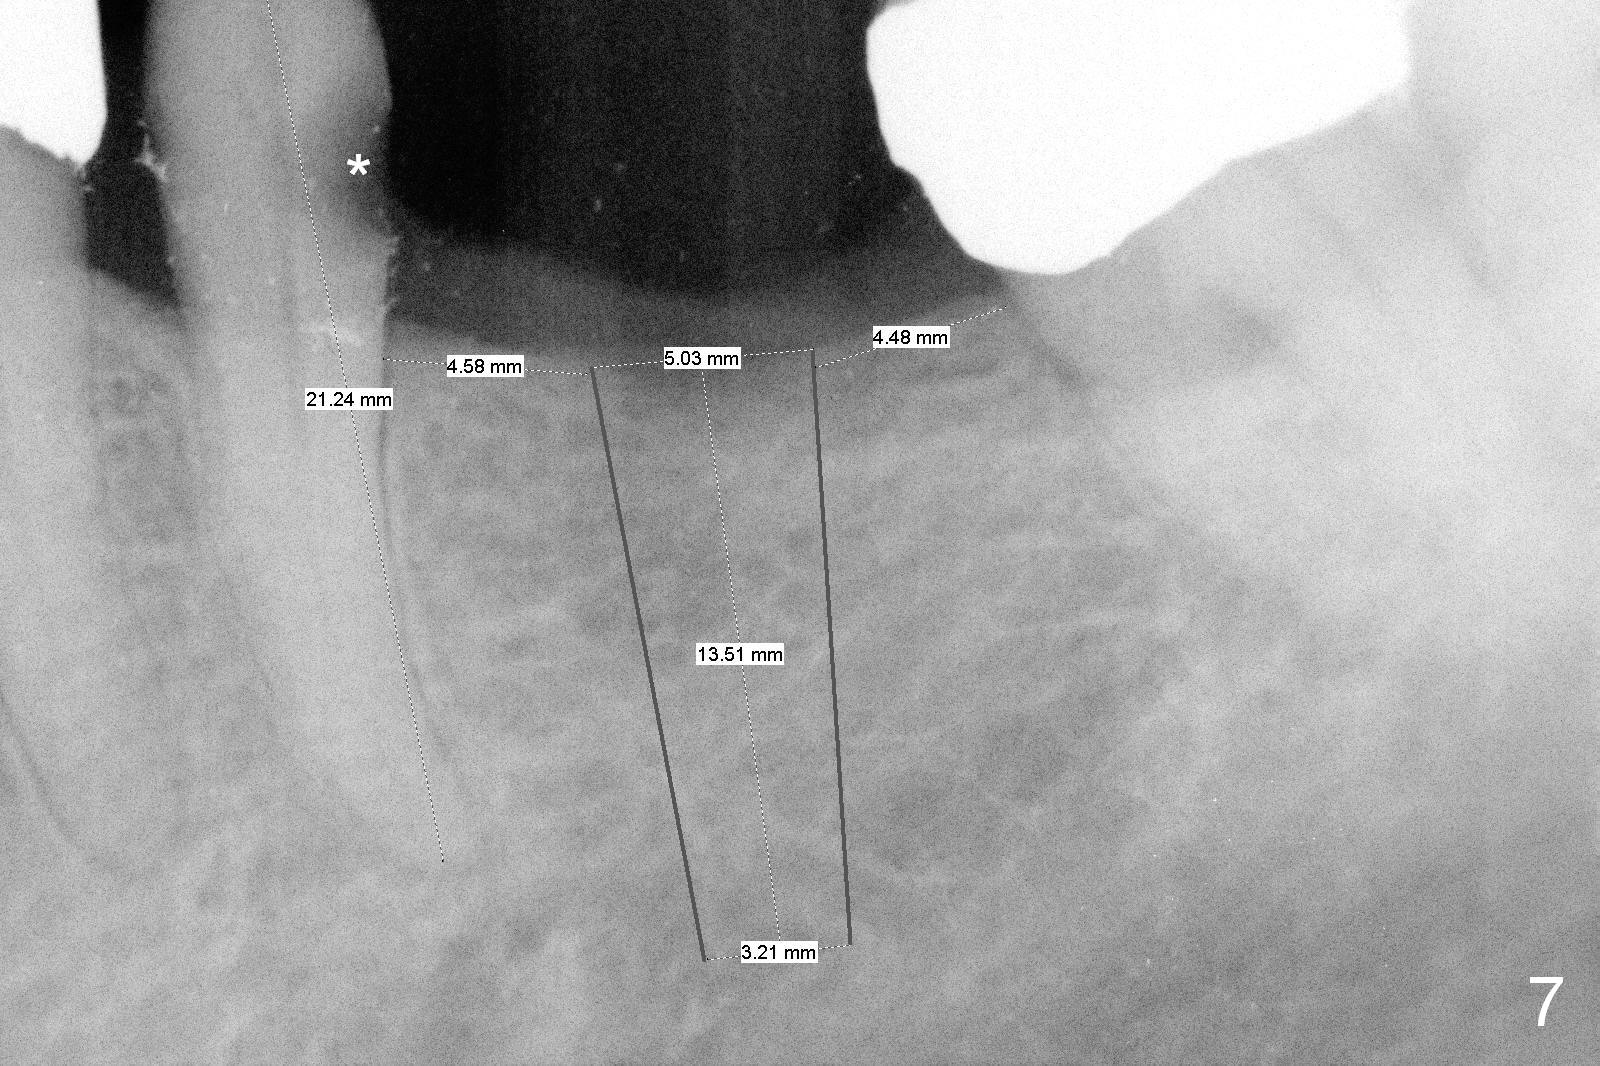

Because of pain, the bridge has been removed partially. Caries in the tooth #20 (Fig.7 *) is confirmed; root canal therapy has been done. With bone expansion, the bone level implant can be placed at the crest. That is, it can be longer (Fig.7: 13.5 mm) than the one placed subcrestally (Fig.2: 10 mm).